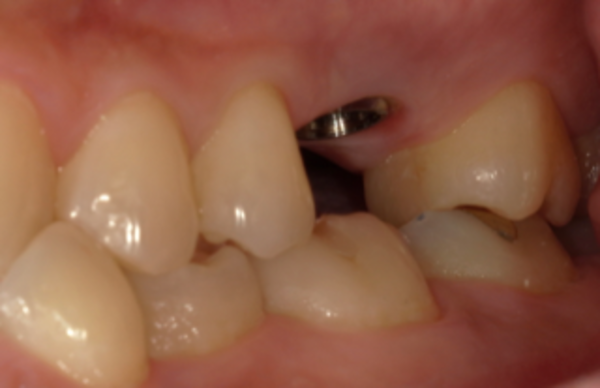

③ インプラント治療

当日来院された際に再度インプラント治療についての確認と同意書を記入していただきました。その後、部分麻酔を行い、インプラントを埋める処置を行いました。

治療後エックス線写真にて埋めたインプラントの確認を行い、問題ないことを確かめ処置終了としました。なお、治療時間は1時間弱でした。

④ 型取り

通常、インプラントと顎の骨とがしっかりと結合する3~4ヶ月後に型取りを行うのですが、患者様のご都合もあり、今回のケースではインプラントの処置後7ヶ月で型取りをしました。